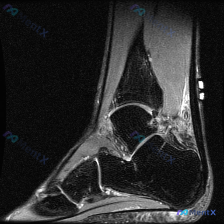

今天给大家分享一张踝关节MRI矢状位T2加权影像的读片分析,病例本身并不复杂,但这种仅表现为少量积液的情况,临床其实很容易走偏,整理一下完整的思考过程给大家参考。 一、影像核心信息整理 这张是踝关节矢状位T2加权MRI,我们先把所有明确的影像信息理清楚: 1. 骨骼结构:胫骨远端、距骨、跟骨、舟骨骨...